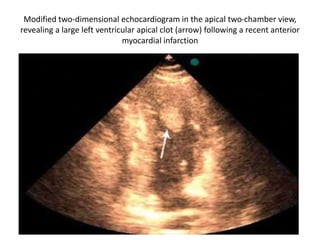

Modified two-dimensional echocardiogram in the apical two-chamber view,

revealing a large left ventricular apical clot (arrow) following a recent anterior

myocardial infarction